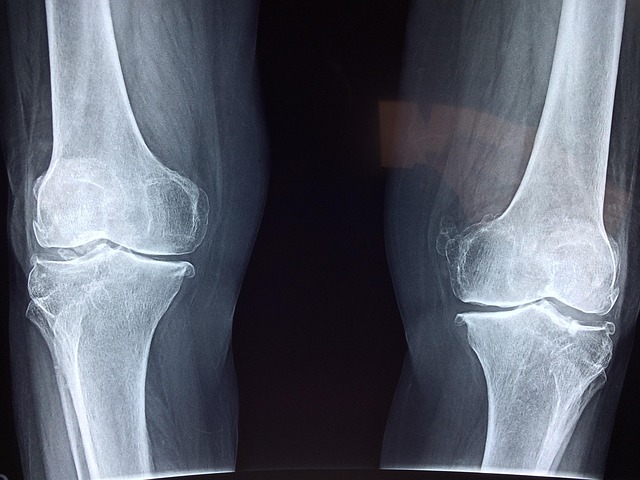

1. 뼈 건강을 위한 필수 영양소, 칼슘

중년이 되면 골밀도 감소로 인해 뼈가 약해지고

골다공증 위험이 증가할 수 있습니다.

이를 예방하기 위해 칼슘(Calcium) 섭취는 필수적입니다.

칼슘은 뼈와 치아를 튼튼하게 유지하는 역할을 하며,

근육 수축과 신경 전달에도 중요한 역할을 합니다.

2. 칼슘 흡수를 돕는 비타민 D

비타민 D(Vitamin D)는 칼슘 흡수를 도와

뼈 건강을 지키는 데 필수적인 영양소입니다.

비타민 D가 부족하면 칼슘이 효과적으로 흡수되지 않아

골다공증과 근육 약화가 발생할 수 있습니다.